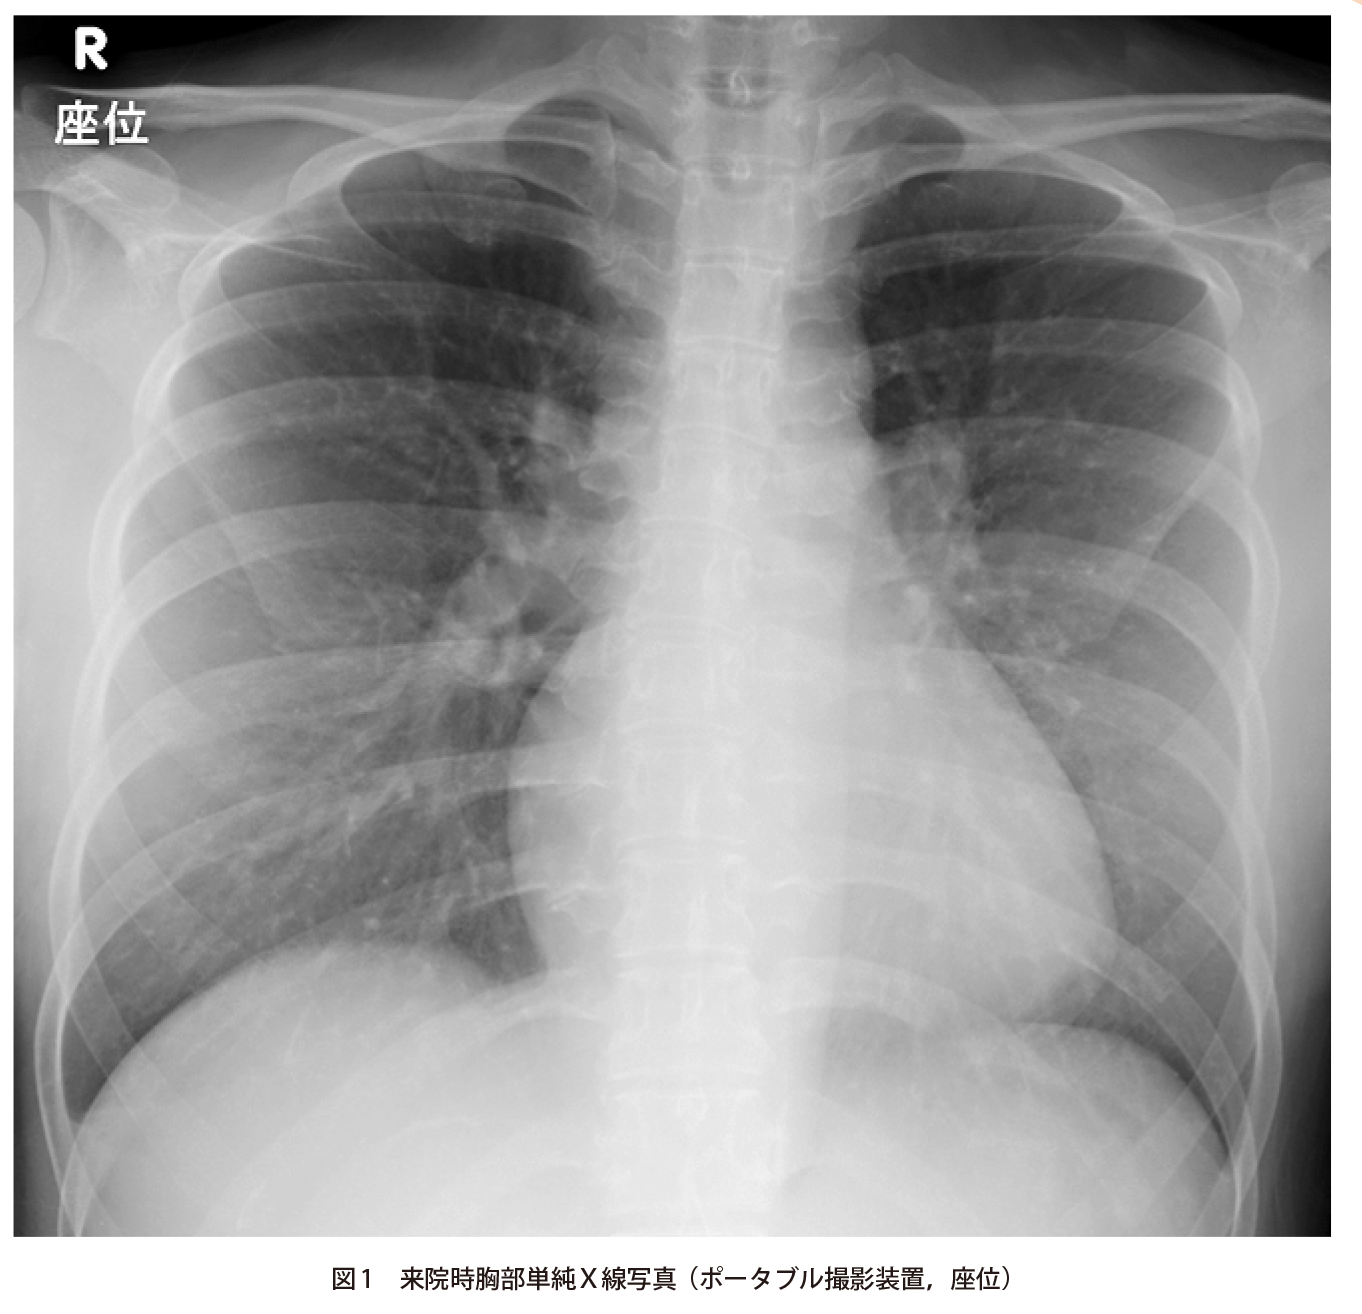

突然の呼吸困難で受診した30歳代女性 実践 画像診断q A 羊土社 レジデントノート 羊土社